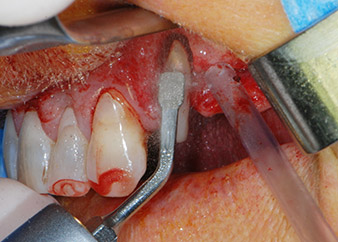

débridement parodontal

Fig. 4 : Pour préserver la dent comme pilier temporaire, un débridement parodontal a été pratiqué à l'aide d'un équipement piézoélectrique...

Nous avons toutefois maintenu notre projet initial de conservation des deux dents comme piliers temporaires d'un bridge pendant la période de six mois nécessaire à l'ostéointégration des implants. À la prochaine incision, la situation devrait être réétudiée. Premièrement, afin de gérer le problème endoparodontal, la surface de racine restante a été soigneusement débridée à l'aide d'un équipement piézoélectrique (Piezomed, W&H, utilisé avec l'insert en forme de spatule S1, initialement conçu pour limer la paroi sinusienne latérale) (Fig. 4).